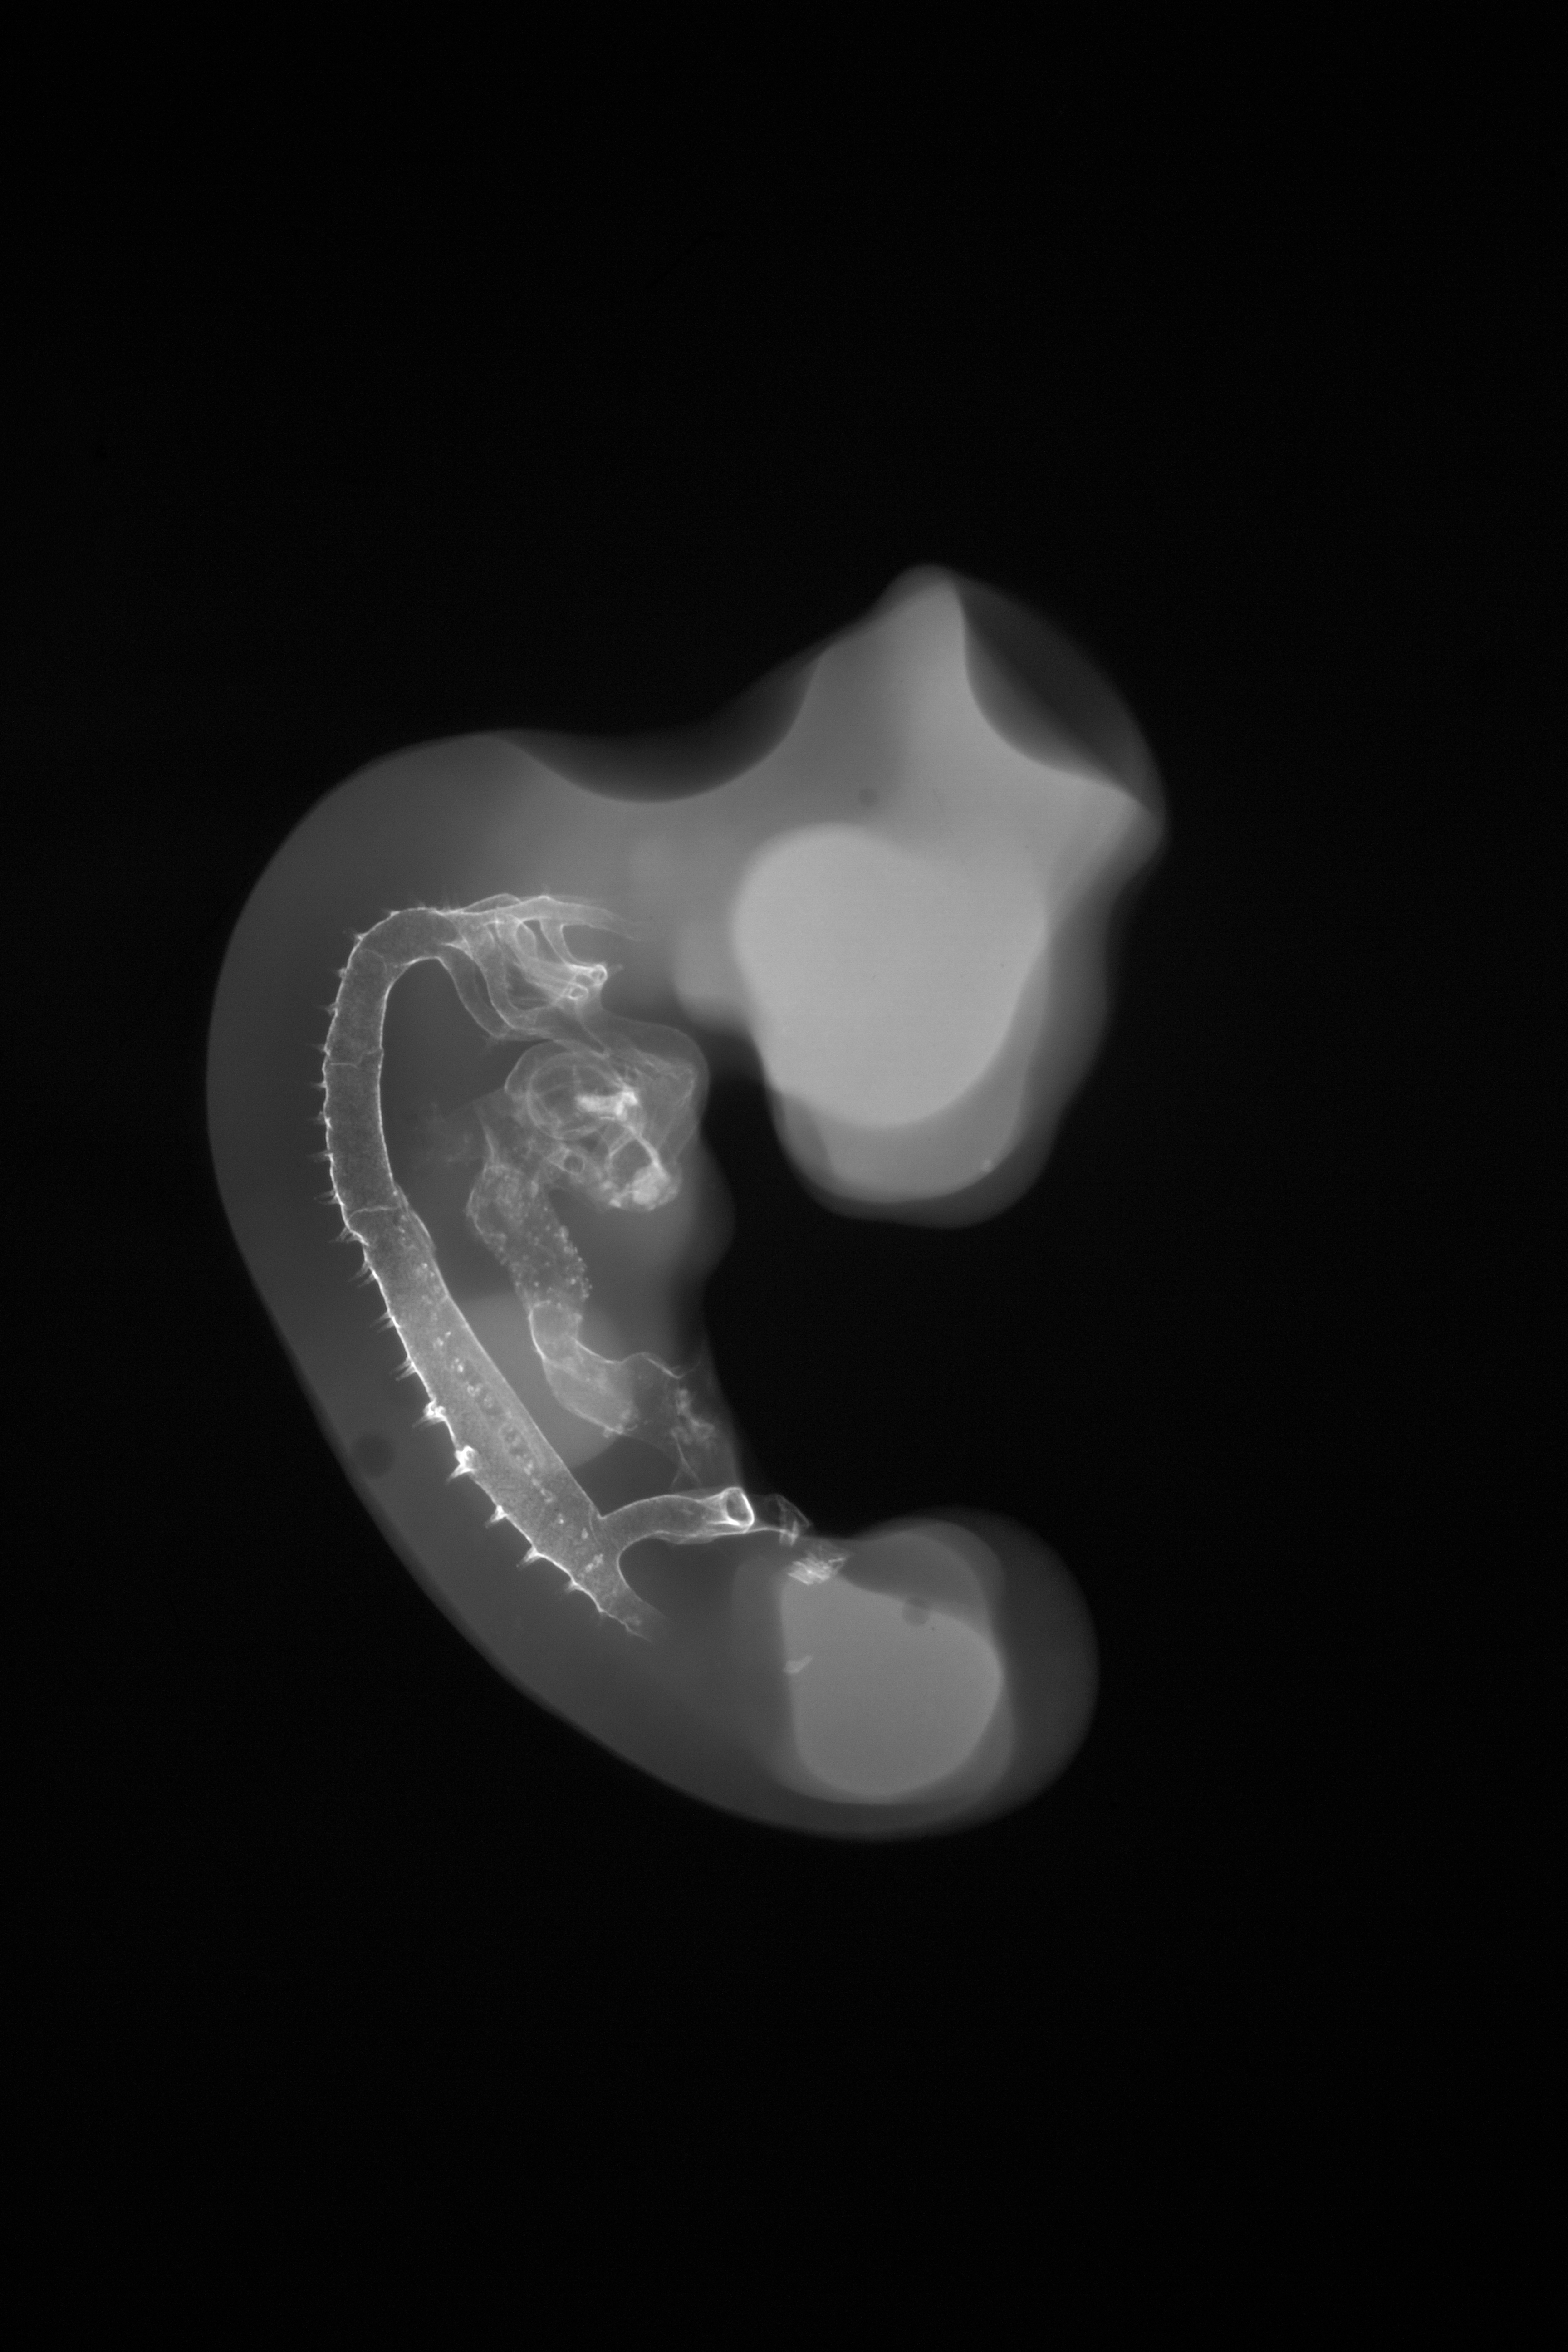

Chick Embryo Microangiography

Hamburger-Hamilton (HH) Stage 21 (approx. 3.5 days)

X-Ray Micrographs